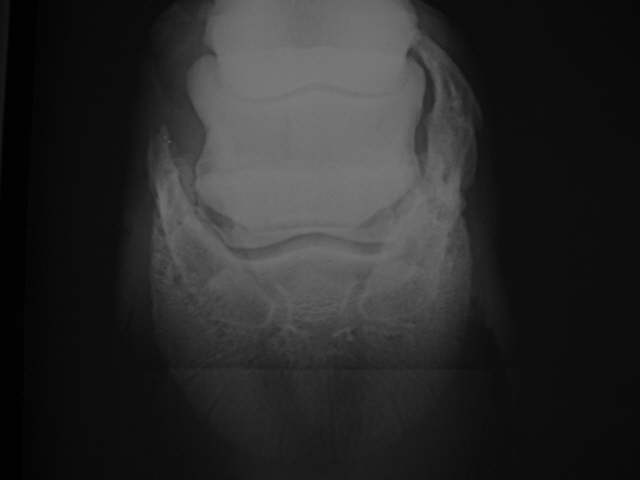

Hufknorpelverkn.

Starke Hufknorpelverknöcherung rechts, die aber bei diesem Pferd keine Lahmheit verursacht hat